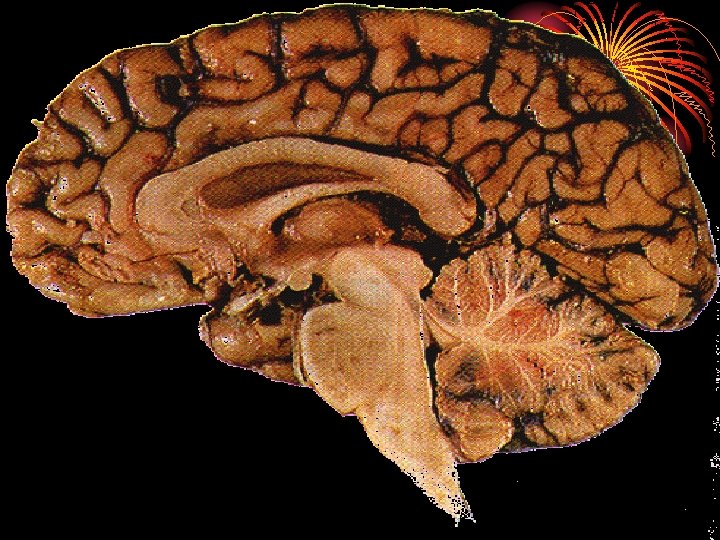

I. The Hindbrain

• The hindbrain is the oldest and innermost region of the brain

• There are three brain areas associated with the Hindbrain: • Medulla • Cerebellum • Pons

• The point at which the spinal cord enters the skull is called the MEDULLA • The MEDULLA controls heartbeat and breathing, blood pressure, and attention

• Extending from the rear of the brainstem is the CEREBELLUM • The CEREBELLUM coordinates voluntary movements and balance (along with the BASIL GANGLIA)

• The PONS is responsible for helping to regulate breathing, to help with sleep and wake cycles, and controls facial expressions

II. The Midbrain • The Midbrain is located between the hindbrain and the forebrain • This area is responsible for coordinating simple muscle movements with changes in sensory information

III. The Forebrain • Areas of the forebrain control thought and reason. • There are five main regions of the forebrain to study: • Thalamus • Hypothalamus • Amygdala • Hippocampus • The Cerebral Cortex

• The CEREBRAL CORTEX is the intricate, wrinkled covering of the brain (FISSURES) (actually a bump is a gyrus and a groove is a sulcus – but that’s a bit too much info…) • In addition to interneurons, it contains GLIAL CELLS, which guide neural connections, provide nutrients to myelin, and mop up neurotransmitters